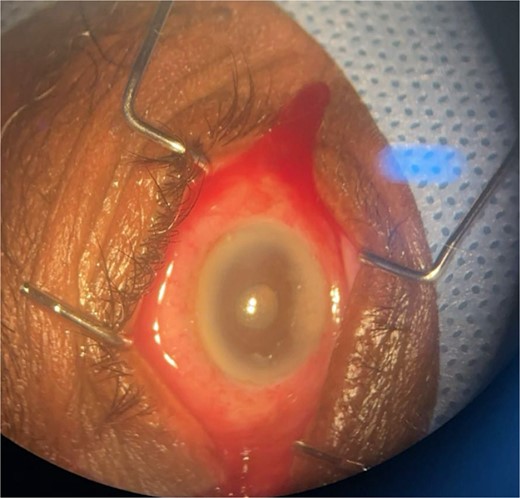

Patient 1: A 66-year-old Sudanese male presented to the emergency room with severe pain in his right eye 2 days post-phacoemulsification. Examination revealed only light perception, elevated intraocular pressure (IOP), a hazy cornea, hypopyon, and extensive pupillary membrane (Fig. 1). A B-scan ultrasound (Fig. 2). He underwent a vitreous tap and received intravitreal antibiotics.

Surgical microscope examination showing hypopyon, chemosis, and conjunctival injection in patient 1.